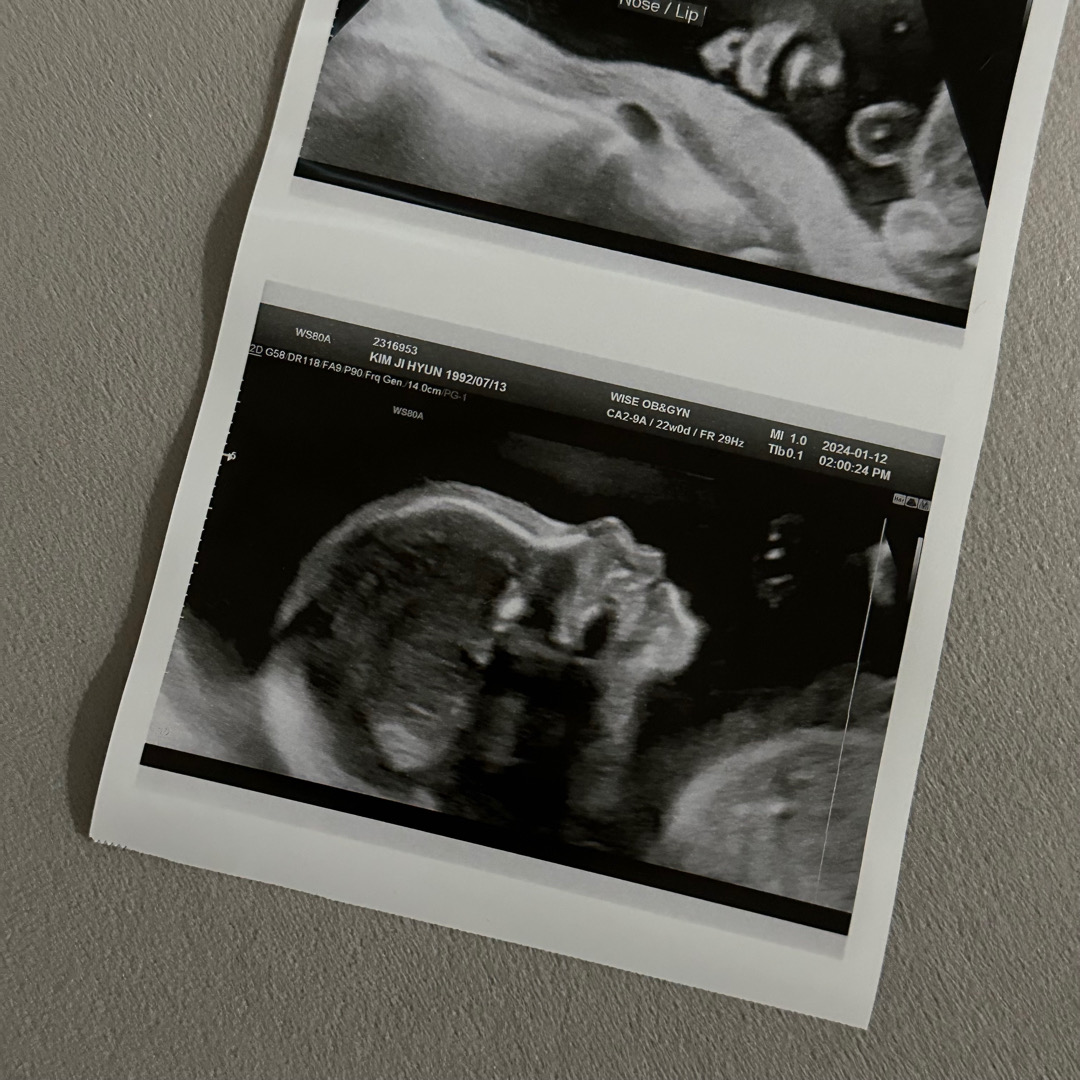

22주 딸 옆모습 자랑하구가여🥹

요정도면 옆모습 이쁜건가요~~~ 제눈엔 걍 이쁨 ㅜㅜ 넘나 예쁨 저 벌써 도치맘이네유 ㅋㅋㅋㅋ 핫🥹